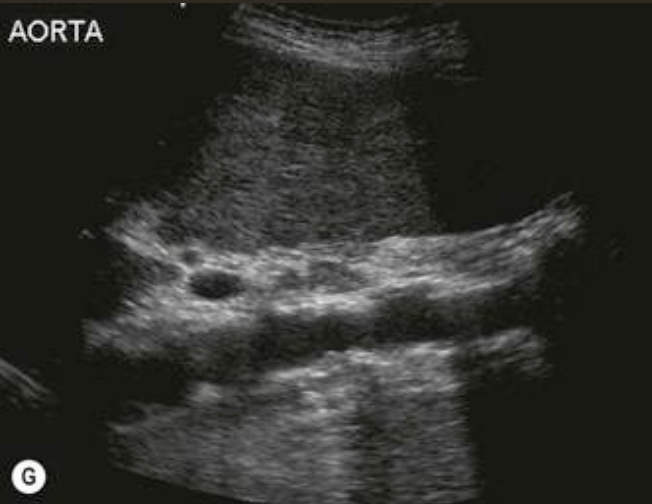

AAA (Abdominal Aortic Aneurysm) → focal dilation of aorta

2D US presentation: focally dilated AO (3 cm or greater), mural hypoechoic thrombus, wall calcifications, usually located infrarenal, can be fusiform or saccular

color doppler: turbulent helical flow

DDX: aortic dissection (aorta may be enlarged, but has intimal flap), pseudoaneurysm (focal outpouching w/ narrow neck, but not all 3 layers involved)